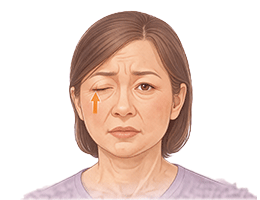

안면마비 (Facial palsy)

안면신경마비 (Facial Nerve Palsy)